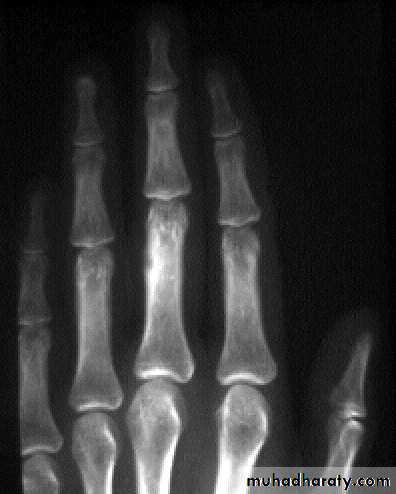

Painless lump on outer or inner table of skullEnchondroma

More in tubular bones of handAccidentally or pain / pathologic #

XR : lytic lesion + flecks of calcification

Malignant risk : 2%

Rx : curettage + bone graftPicture 4. Frontal radiograph of the right thigh demonstrates coarse calcifications in the distal femur.